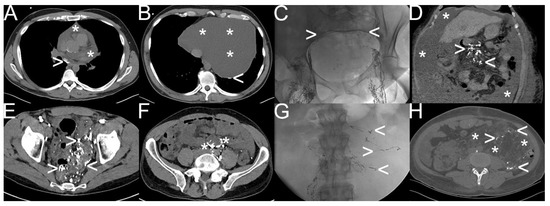

Figure 5.

Different types of iatrogenic lymphatic fistulas detected by “conventional lymphangiography“. Note: (A,B) after robot-assisted prostatectomy—iliac lymphocele (white arrowhead); (C,D) after total-knee arthroplasty—lymphatic feeder (white arrowhead) and percutaneous lymphatic fistulas (black arrowhead) leading to wound-healing disorder; (E–H) after radical thyroidectomy—mediastinal lymphatic fistula from the thoracic duct (white arrowhead) draining into the intraoperatively inserted drainage tube (white asterisk); (I,J) after soft tissue resection—typical lymphocele with blowout of oil-containing contrast material; (K,L) after chemotherapy for non-Hodgkin’s lymphoma—chylaskos (white asterisk), and chylothorax with pathological accumulation of the oil-containing contrast material in retroperitoneal and mesenteric lymph nodes; (M–P) postoperative lymphocele (white arrowhead) and lymphatic feeder (black arrowhead) with impaired lymphatic run-off in the calf (black arrowhead) in contrast to a healthy lymph node (white asterisk) and a healthy lymph duct (black asterisk); (Q–T) after cardiac surgery—refractory chylothorax and chylopericardium with multifocal pathologic extravasation and accumulation of oil-containing contrast material in the mediastinum (white arrowhead).